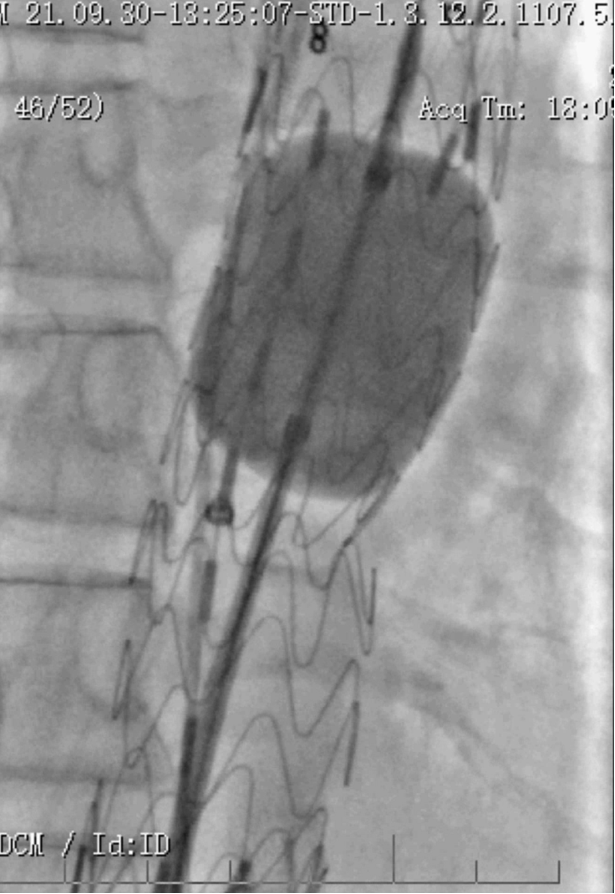

病例1 两开窗:

病例2 四开窗:

手术时间382分钟

造影剂用量320ml